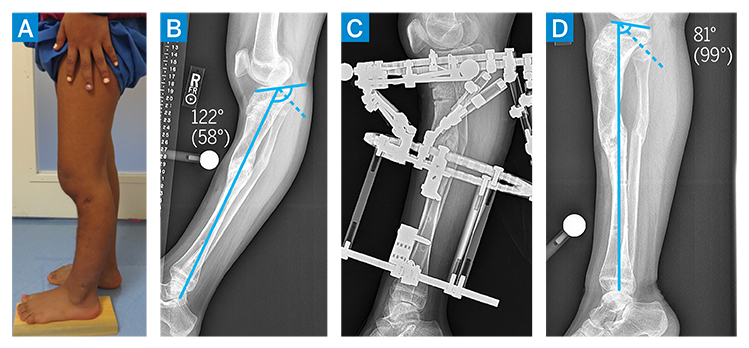

The patient underwent right proximal tibial epiphysiodesis, fibular osteotomy, and distraction osteoplasty with a hexapod frame. The nonunion was found to be nonosseous and hypertrophic in nature, allowing for correction through the nonunion site without need for additional osteotomy. The intramedullary canal proximal and distal to the nonunion site was drilled, and intraoperative cultures were obtained to confirm absence of ongoing infection. A hexapod ringed external fixator was applied to allow for simultaneous correction of the varus deformity and gradual lengthening (Fig. 2A). By 2 months postoperatively, the patient’s varus deformity was significantly improved and limb length discrepancy had improved to 3 cm (Fig. 2B–C). Her external fixator was removed 3 months postoperatively, with a residual recurvatum deformity noted (Fig. 3A–B). Shortly thereafter, she underwent right proximal tibial metaphyseal osteotomy and gradual deformity correction with a hexapod ringed external fixator (Fig. 3C). By 3 months postoperatively, coronal and sagittal alignment were normalized and the external fixator was removed (Fig. 3D).

Figure 3

Figure 3: (a–b) Preoperative imaging demonstrating persistent recurvatum deformity. (c–d) Postoperative imaging demonstrating external fixator and proximal tibia osteotomy, resulting in normalization of tibial slope.